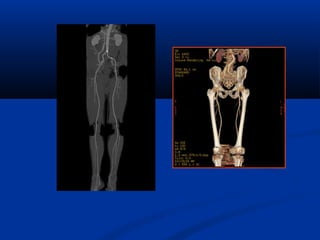

Xaùc ñònh vò tríxöông söôøn treân CT